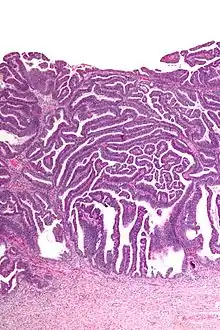

The name of the lesion describes it microscopic appearance. It has nipple-like structures with fibrovascular cores (papillae) that are long in relation to their width (villus-like), which are covered with a glandular pseudostratified columnar epithelium.

Micrograph of a villoglandular adenocarcinoma the cervix. H&E stain.

Very high magnification